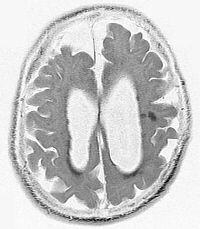

Brain Degeneration

Tau-Related Brain Degeneration

(anterior at top)

It has long been recognized that the amyloid-β plaques found in Alzheimer’s Disease, the α-synuclein found in Parkinson’s, and phosphorylated tau (tau tangles) found in a number of neurological disorders, including Alzheimer’s, Corticobasal Degeneration (CBD), etc., as well as the superoxide dismutase 1 associated with amyotrophic lateral sclerosis (ALS, Lou Gehrig’s Disease) are all misfolded forms of normal brain proteins. Tau, for example, is normally a long, straight-stranded protein that helps microtubules in neurons to do their jobs. When tau becomes phosphorylated, it crumples up into tangled balls consisting of multiple strands of tau, and interferes with normal microtubule structure and function. It has been known that tau tangles are able to leave “their” neuron, travel to and into another neuron, and once there, cause the tau in that neuron to also tangle, to the point that it becomes possible to correlate the path of the spread of tau tangles in the brain with the progression of Alzheimer’s symptoms. For a number of years, in the 2000s, as these proteins were being studied, researchers initially said this behavior was “similar to” the behavior of prions, but I’m seeing increasing numbers of recently-published (as of 2011, 2012, 2013, etc.) articles that just out-and-out call all of these misfolded-proteins prions. Researchers have injected purified tau and/or amyloid-β into the bloodstream of mice, then several months later, found Alzheimer’s-type changes in the mice’s brains, demonstrating that Alzheimer’s is communicable. Thus, they have conjectured that blood transfusions from someone with early-stage, undetected, asymptomatic Alzheimer’s (or other degenerative neurological disease), surgical, especially neurosurgical, equipment that has not been prion-sterilized, and/or transplacental transfer from mother to baby in a pregnant woman may, possibly serve as sources of prion inoculation in an individual. Again, in their normal native conformation, these are all important, useful brain proteins, but when they become denatured/misfolded, they “turn into” infective prions.